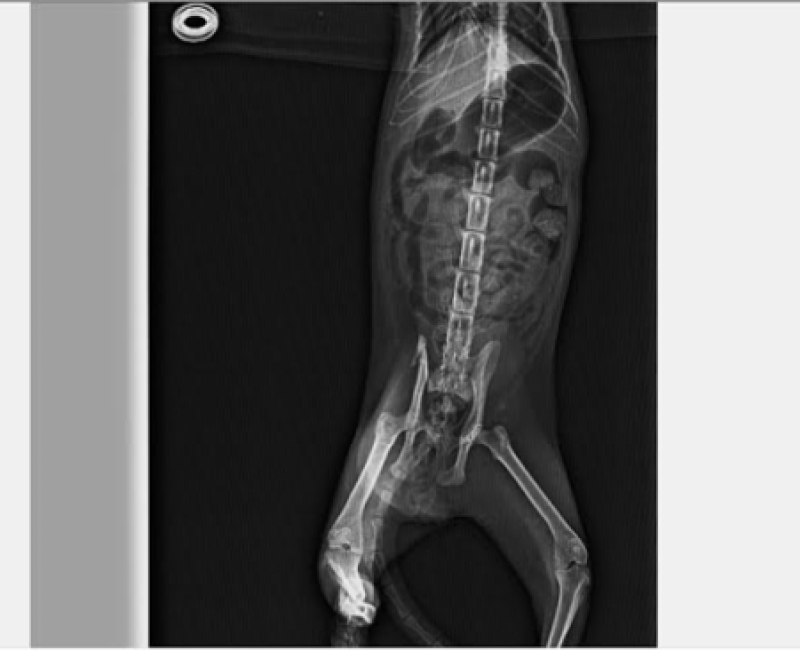

BOTITAS, ATROPELLADA Y DEJADA A SU SUERTE Botitas fue atropellada y dejada en la calle como si de un despojo se tratara... Tras llevarla al veterinario y hacerle varias radiografías hemos comprobado que tiene la tibia y el peroné rotos, así como luxación de ambos lados de la pelvis. Ha sido operada de urgencia. Cuando se recupere podrá buscar hogar, pero ahora mismo busca una acogida indefinida para que pueda recuperarse tranquila. Necesitamos ayuda para pagar el veterinario y todos sus gastos. ¿ Nos ayudas?. Escríbenos a: felinalahuellaroja@gmail.com